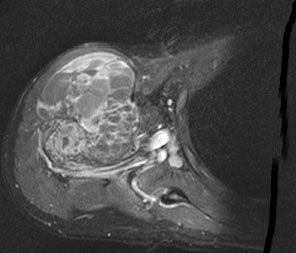

| Diagnostik | MRT- Bild eines Osteosarkoms des Humerus![]() | ||